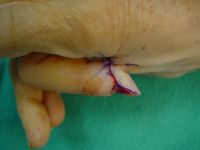

| Flap inset,

bringing the thumb to the finger. |